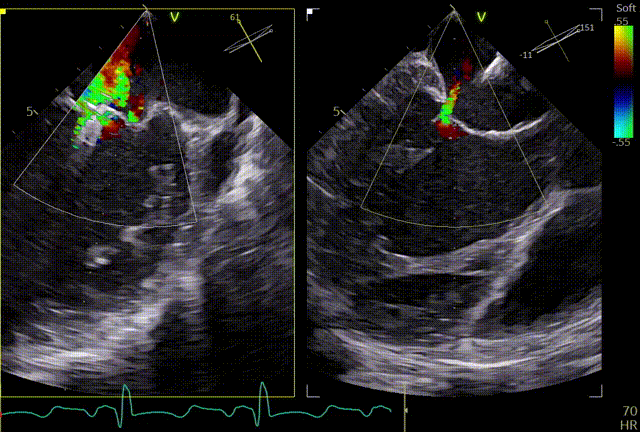

反流情况

1区带彩

2区带彩

3区带彩

3D带彩